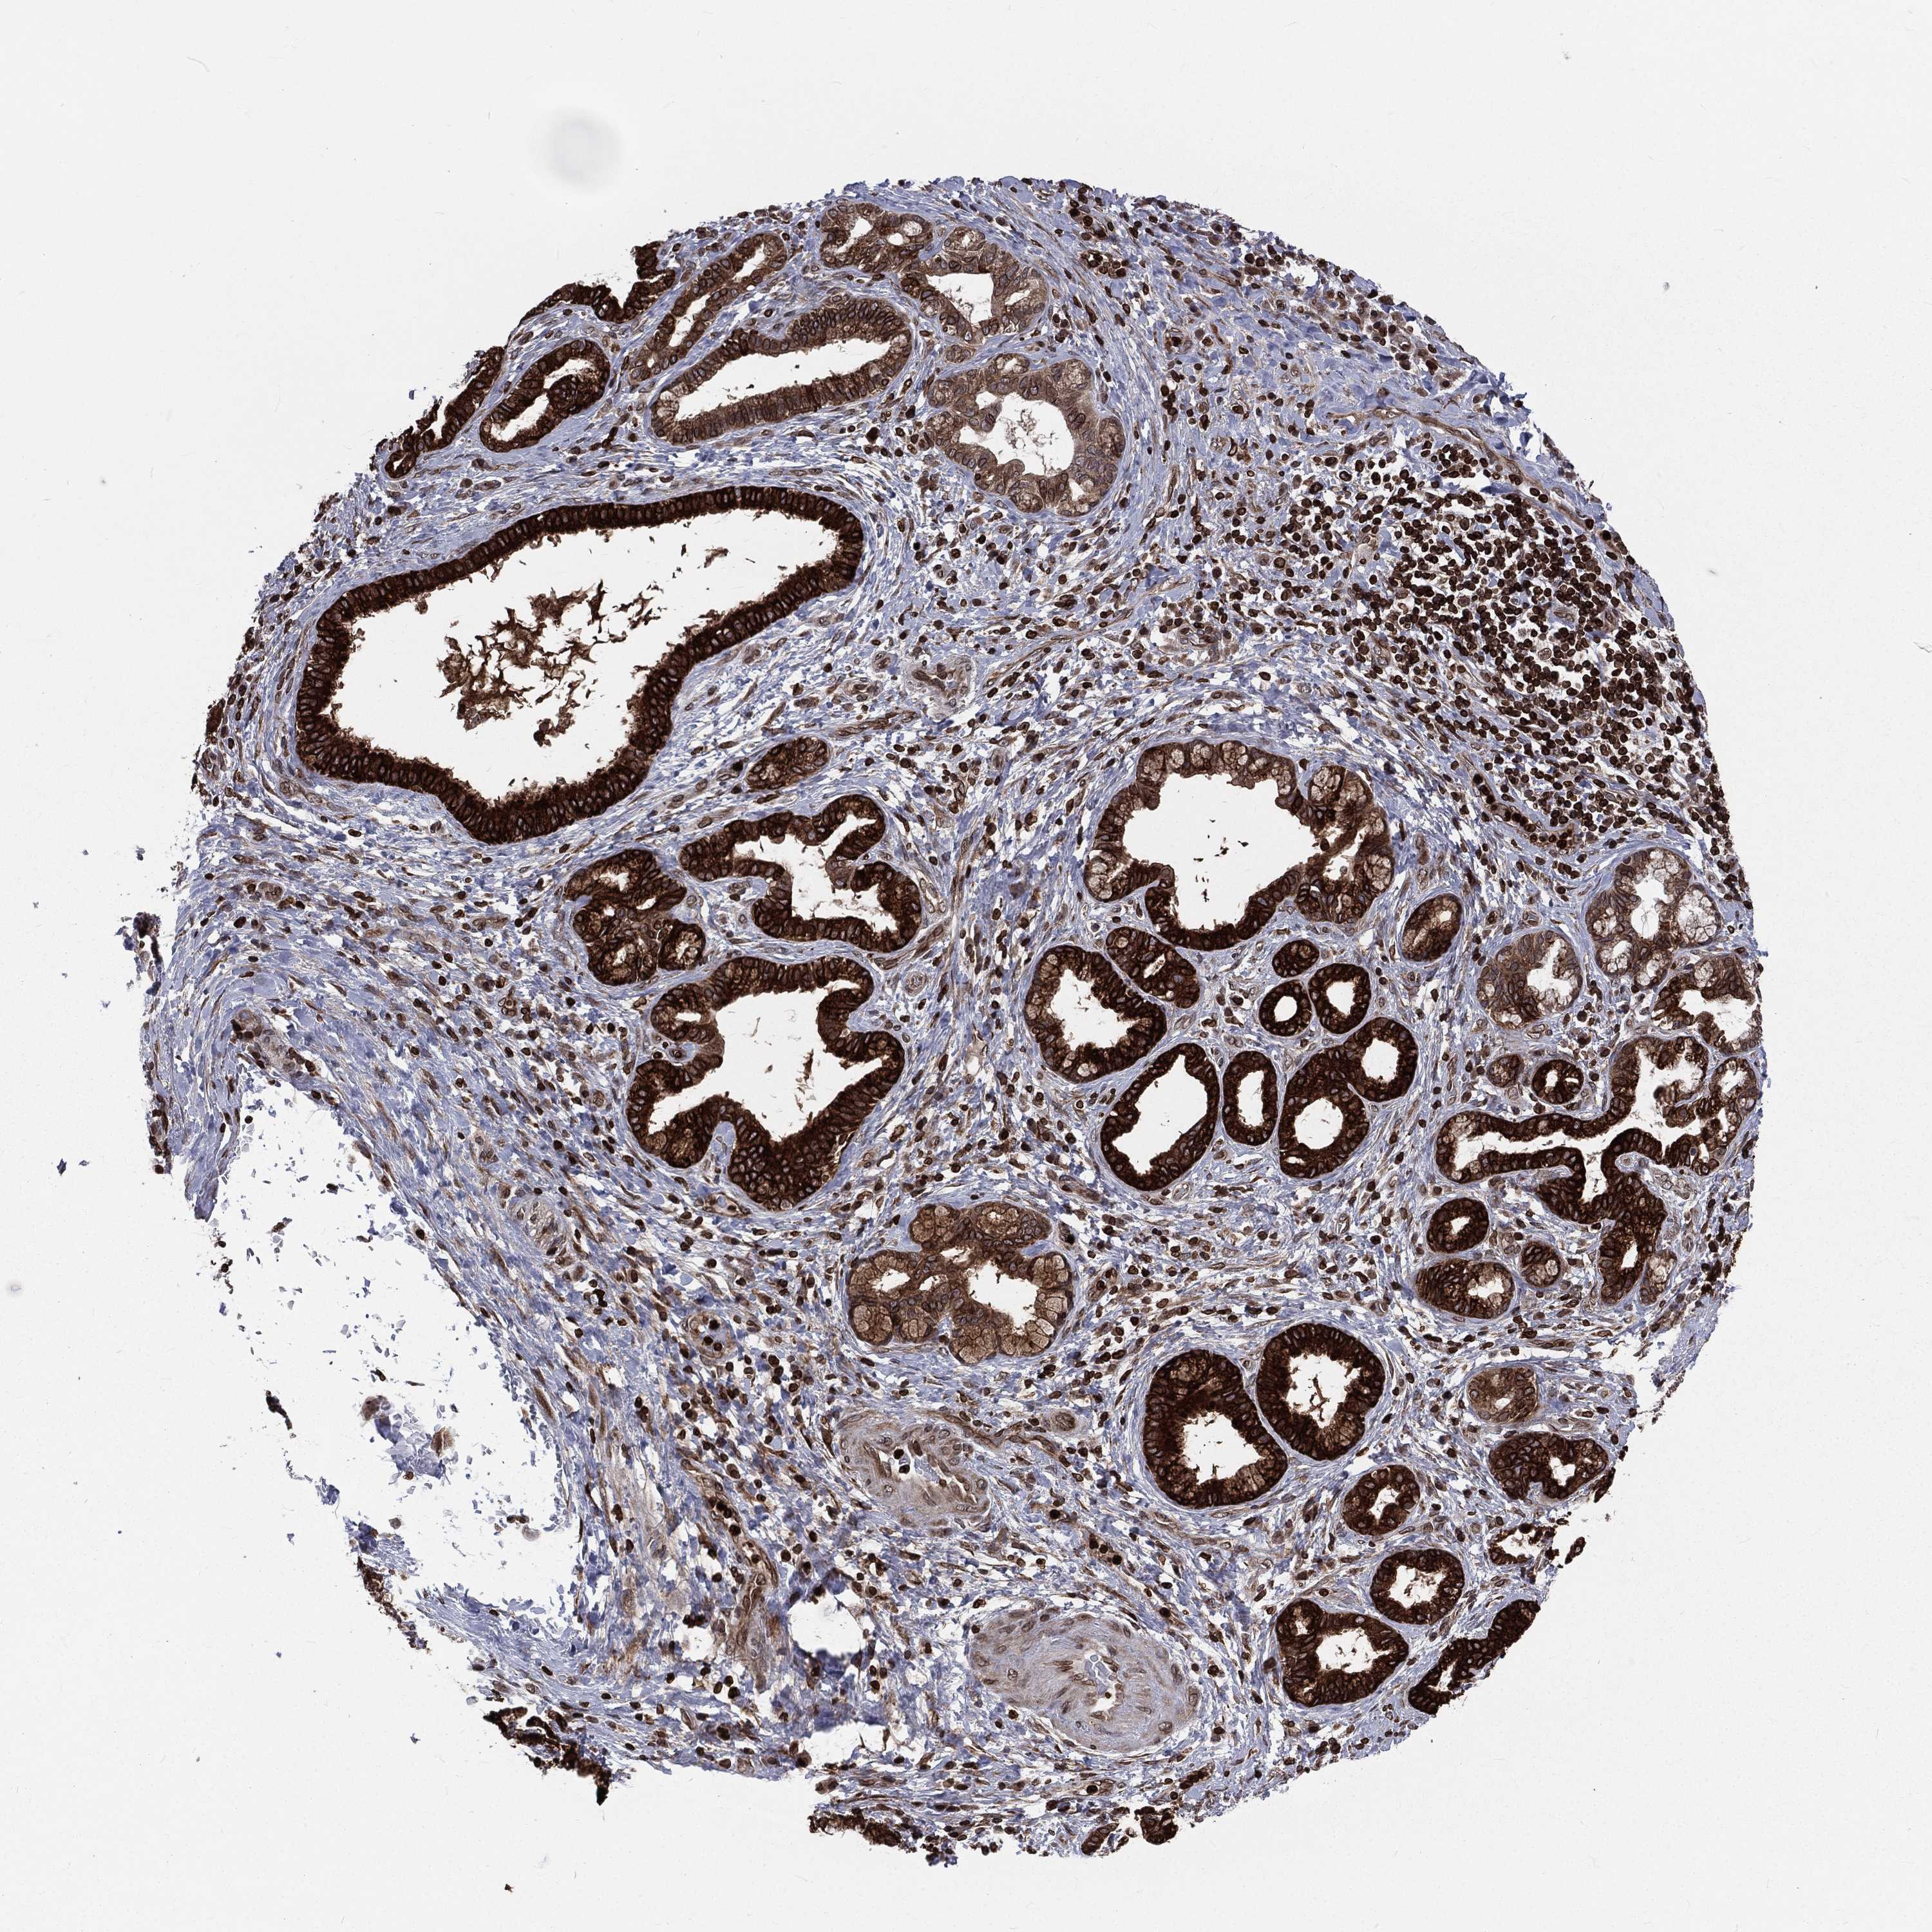

LIVER CANCER - Protein expressioni

A mouse-over function shows sample information and annotation data. Click on an image to view it in a full screen mode. Samples can be filtered based on level of antibody staining by selecting one or several of the following categories: high, medium, low and not detected. The assay and annotation is described here.

Note that samples used for immunohistochemistry by the Human Protein Atlas do not correspond to samples in the TCGA dataset.

Antibody stainingi

Antibody staining in the annotated cell types in the current human tissue is reported as not detected, low, medium, or high, based on conventional immunohistochemistry profiling in selected tissues. This score is based on the combination of the staining intensity and fraction of stained cells.

Each image is clickable and will lead to virtual microscopy that enables deeper exploration of all samples and also displays staining intensity scores, fraction scores and subcellular localization as well as patient and tissue information for each sample.

Antibody HPA049840

Antibody HPA062236

Staining

High

Medium

Low

Not detected

Intensity

Strong

Moderate

Weak

Negative

Quantity

>75%

75%-25%

<25%

None

Location

Nuclear

Cytoplasmic/membranous

Cytoplasmic/membranous,nuclear

Cholangiocarcinoma

Carcinoma, Hepatocellular, NOS